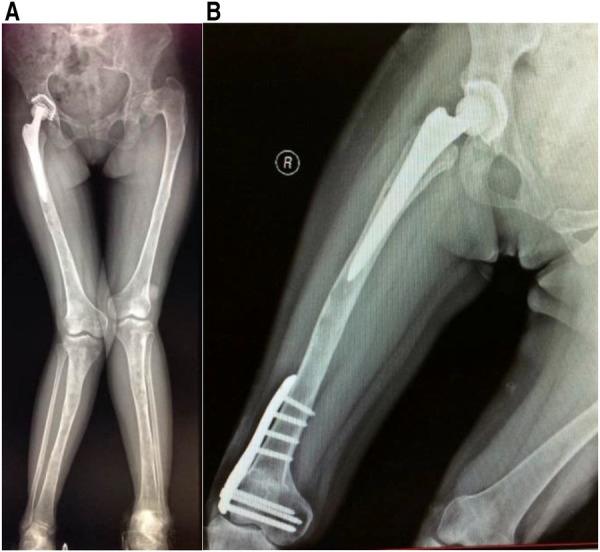

患者2009年至2013年间接受了四次静脉输注唑来膦酸5mg,同时口服补钙。2010年7月进行右侧全髋关节置换术(THA)。术后髋关节X线片见图1。碱性磷酸酶和骨钙素水平分别为538 IU/L和192.5 ng/ml。2013年12月,患者接受了矫形外科手术和右髁上截骨(图2)。入院时,碱性磷酸酶和骨钙素水平为403 IU/L和246.30 ng/ml。2015年5月,患者因跌倒导致左股骨干骨折,并接受了钢板和螺钉内固定(图3)。根据术后组织病理学,最终诊断为纤维发育不良。2015年12月,移除右侧股骨板,以防止应力集中和随后的股骨干骨折。尽管患者在随访期间没有出现明显并发症,但于2017年和2018年在另一家医院接受了颌下感染和下颌骨坏死的治疗(图4)。

图2 (A) 术前下肢X线片。(B) 右膝外翻矫正术后X光检查